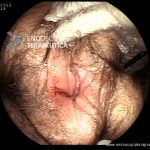

Colite por Doença de Crohn

- Doença de Crohn em atividade

- Doença de Crohn em atividade – proctite